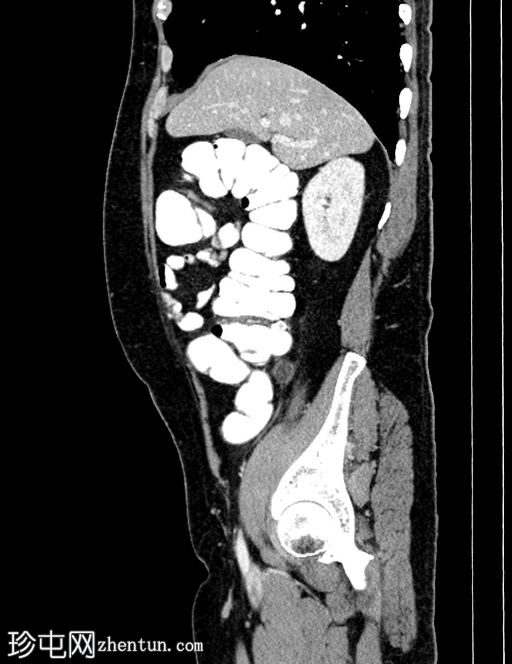

轴位

平扫

平扫CT显示,盲肠后外侧壁旁可见一边界清晰的卵圆形脂肪密度影,周围环绕一薄层高密度环(“高密度环”)。周围脂肪间隙轻度改变,无游离液体,邻近结肠壁未见增厚。动脉期,病灶仍为脂肪密度影,高密度环略有强化;未见动脉出血。